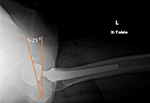

| Bilateral total hip arthroplasty (THA) |

38 year old man with bilateral THA for advanced osteoarthritis. On a true cross-table lateral view of the hip there is normally 5-25 degrees of anteversion which is measured as the angle between the rim of the acetabular cup and a line drawn perpendicular to the horizontal surface. |